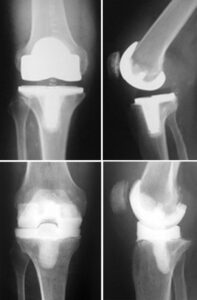

Total knee and hip replacements are among the most commonly performed elective surgeries, significantly improving the quality of life for many patients by relieving pain and enabling them to engage in more active lifestyles.

Infections related to joint replacements can either affect the surgical wound or develop deep within the area surrounding the artificial implants, which are made of metal and plastic. These infections can arise during the hospital stay or after the patient returns home, and in some cases, they may even occur years later.